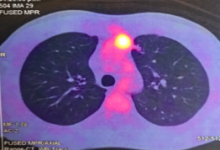

A 32-year-old man was referred with a diagnosis of an extragonadal germ cell tumor in the anterior mediastinum. Initially, he was treated with four cycles of chemotherapy (bleomycin, etoposide phosphate, and cisplatin), after which a PET-CT demonstrated a persistent hypermetabolic mass (SUV max 7.8) in the anterior mediastinum measuring 48 x 32 x 70 mm, without other metabolic abnormalities. Alpha-fetoprotein (AFP), LDH, and human chorionic gonadotrophin serum levels were normal. A radical surgical resection was recommended due to persistent residual disease. It was performed via a sternotomy with mediastinal tumor resection, pulmonary segmentectomy, and left diaphragm plication, due to resection of the involved phrenic nerve. The pathology results showed an embryonal carcinoma, 90 x 70 x 40 mm, with lung parenchyma involvement and 24% necrosis. There was no lymphovascular invasion, 1 of 4 lymph nodes had metastasis, and the margins were negative. Markers CD117 and CD30 were positive, AFP was negative. The patient recovered well. He was discussed in a tumor conference and was recommended to undergo adjuvant chemotherapy followed by bone marrow transplant.

PET – CT: Persistence of a hypermetabolic residual mass (SUV max 7.8) of 48 x 32 x 70 mm is observed in the anterior mediastinum.